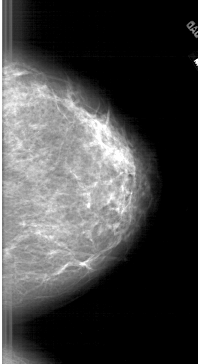

A_1905_1.LEFT_CC

LEFT_CC LINES 5671 PIXELS_PER_LINE 2881 BITS_PER_PIXEL 12 RESOLUTION 43.5 OVERLAY